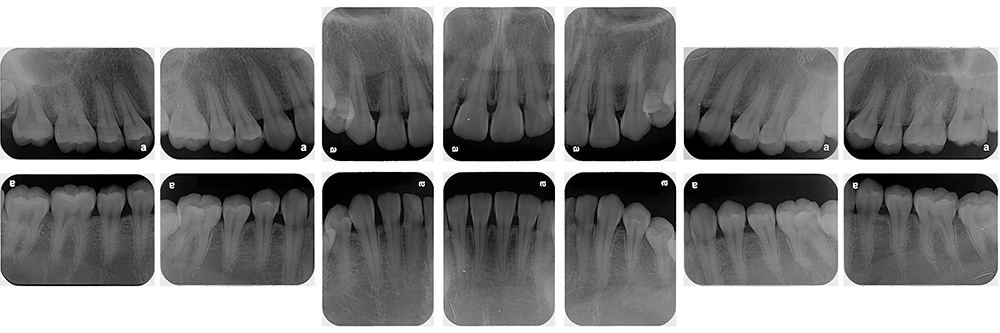

術前

術後

世代・性別

30代女性

主訴

歯がしみる時がある

治療内容

セラミックインレー

治療期間

2回

治療費

66,000円(税込)

治療のリスク

強い咬合力や衝撃によって、欠けたり割れたりすることがある